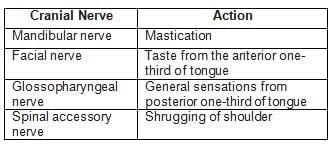

Match the following cranial nerves with their corresponding actions: (INI-CET May 2023)